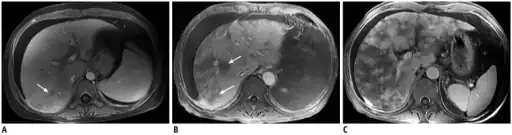

Post contrast-enhanced MR images show severity of patchy liver enhancement in hepatic sinusoidal obstruction syndrome.A. Grade 1. Arrow denotes mild patchy enhancement. B. Grade 2. Arrows denote moderate confluent patchy enhancement. C. Grade 3. Severe case with diffuse confluent patchy enhancement. Note all three cases demonstrate ascites.